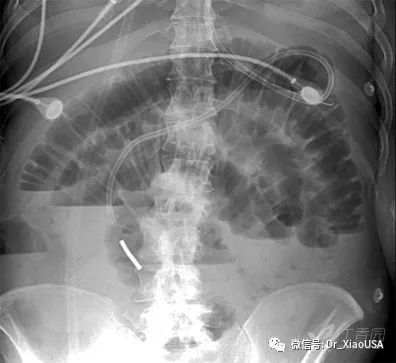

16.小肠梗阻典型平片表现是什么?

a) 小肠扩张(平卧位):>6cm

b) 气液平面(直立位)

17.结肠梗阻的典型平片表现是什么?

a) 结肠扩张:>8cm